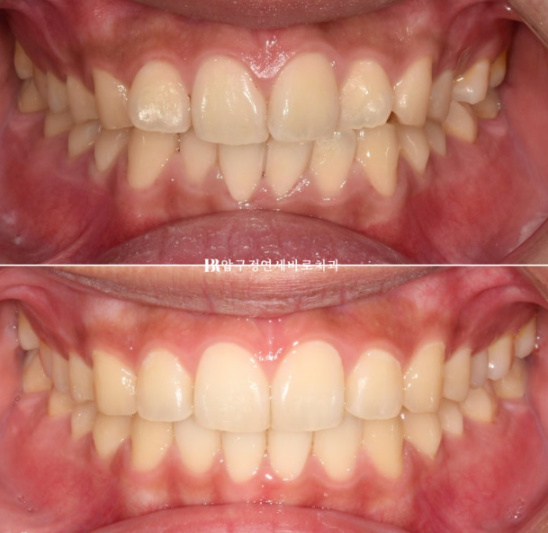

23.12

1년 전 인비절라인 교정을 위해 내원하신 환자분입니다.

삐뚤한 앞니가 보입니다.

결론적으로 치료에 잘 응해주셨으며 좋은 결과를 볼 수 있었습니다.

24.10

걱정하시는 교합도 좋습니다.

인비절라인은 교합이 안 좋게 끝난다 라는 편견을 깨기 위해 노력합니다.

23.12~24.10

배열도 좋습니다.